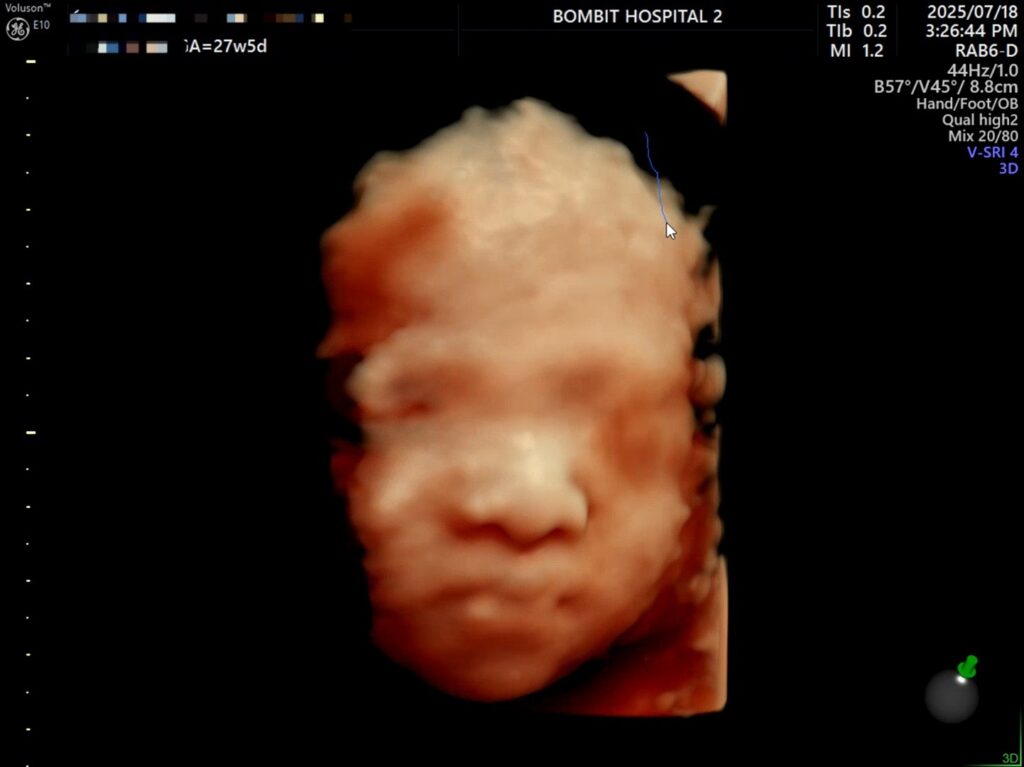

그렇게 다행스럽게도 단비 얼굴을 볼 수 있게 되었다.

체중은 상위 84%, BPD(머리 폭)이 상위 97%다. FL(대퇴골 길이)도 상위 91%..

우량우량..ㅋㅋ

입초로 본 단비 얼굴은 정말 너무너무 귀여웠다!! 보면서 코가 복코같이 눌려있다고 생각했는데,, 선생님은 아기 콧대가 높다고 했다. 엄마를 닮아서 그런 듯(?)ㅋㅋㅋ

오빠도 단비 사진을 보더니 너무 이쁘다고 했다. 그래서 걱정된다며..ㅎㅎㅎ